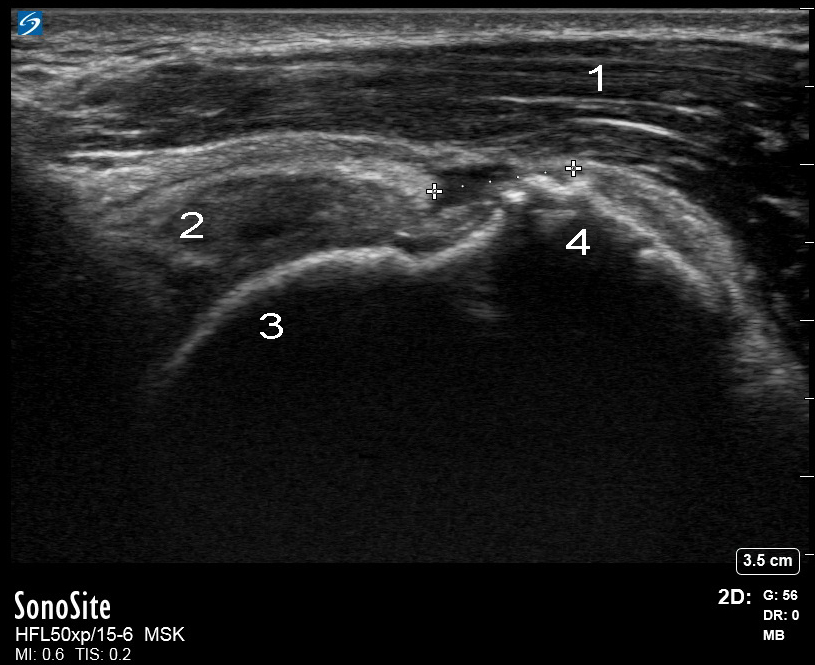

Shoulder Supraspinatus Tendon Bursal Surface Tear Image

Left Supraspinatus Longitudinal Axis (LAX)

1. Deltoid

2. Supraspinatus

3. Humeral Head

4. Greater Tuberosity (GT)